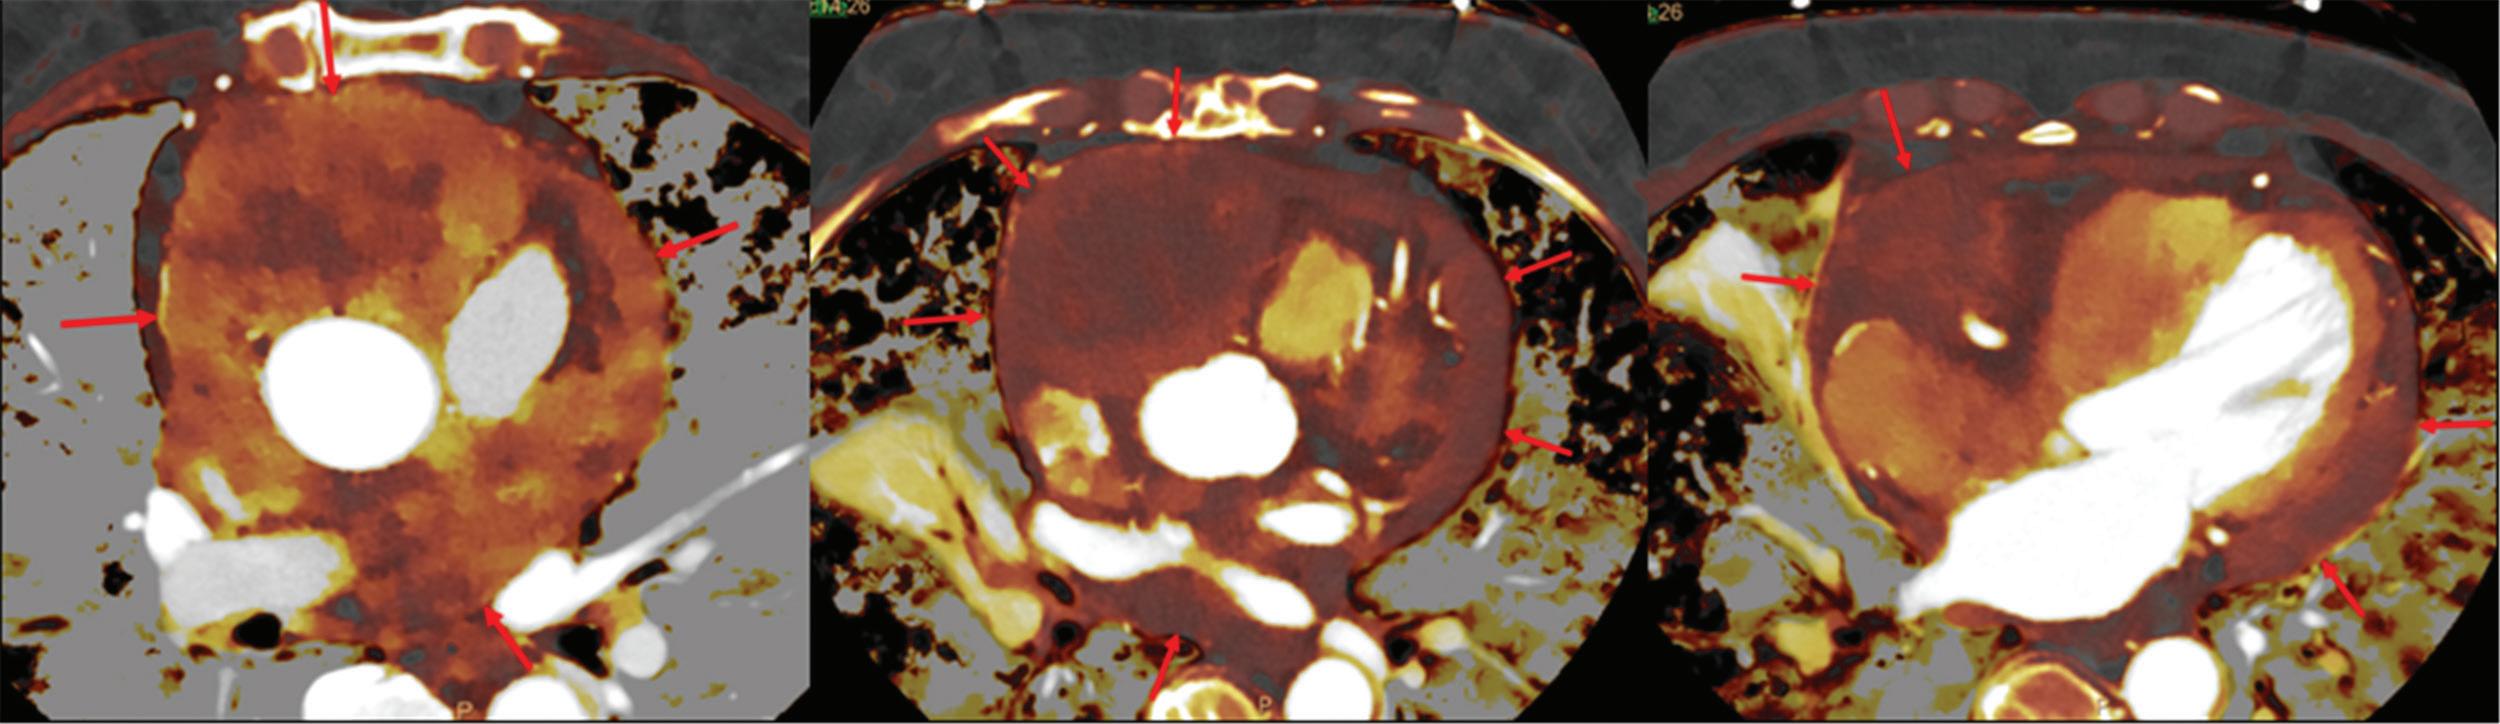

A

referred

CT

breath-hold results in a poor enhancement of the pulmonary arteries on the

CT images.

displays from left to right: monoenergetic 70 keV, monoenergetic 55 keV, monoenergetic 40 keV, and Z effective map showing a perfusion deficit of the lung parenchyma (white arrow). When decreasing the energy, the iodine attenuation is progressively boosted and reveals the presence of a thrombus (colored arrows) in a sub-segmental pulmonary artery corresponding to the territory of the perfusion deficit. (c) Monoenergetic 200 keV reduces beam hardening from dense contrast medium compared to conventional CT images.

10

Figure 2

A C B Clinical case collection

patient

to

for suspicion of pulmonary embolism. (a) A Valsalva maneuver during

conventional

(b) Magic Glass